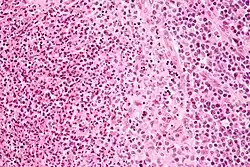

Micrograph of a lymph node affected by cat scratch disease. H&E stain.

High-magnification micrograph of CSD showing a granuloma (pale cells - right of center on image) and a microabscess with neutrophils (left of image), H&E stain

Cat-scratch disease is characterized by granulomatous inflammation on histological examination of the lymph nodes. Under the microscope, the skin lesion demonstrates a circumscribed focus of necrosis, surrounded by histiocytes, often accompanied by multinucleated giant cells, lymphocytes, and eosinophils. The regional lymph nodes demonstrate follicular hyperplasia with central stellate necrosis with neutrophils, surrounded by palisading histiocytes (suppurative granulomas) and sinuses packed with monocytoid B cells, usually without perifollicular and intrafollicular epithelioid cells. This pattern, although typical, is only present in a minority of cases.[16]